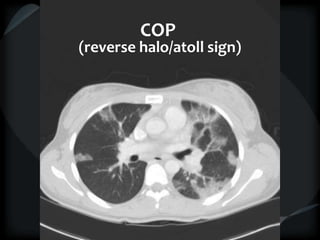

Airspace Patterns

 Reverse halo/atoll sign

 Organising pneumonia – COP/BOOP

COP

(reverse halo/atoll sign)

Airspace Patterns  Diffuseground-glass  Patchy consolidation (peripheral)  Inter and intralobular septal thickening / ground glass/crazy paving  Reverse halo/atoll sign  Hogshead cheese sign  Perilobular pattern  Organising pneumonia – COP/BOOP  Chronic eosinophilic pneumonia  Alveolar proteinosis  Desquamative interstitial pneumonitis  Alveolar microlithiasis  Alveolar sarcoid  BAC